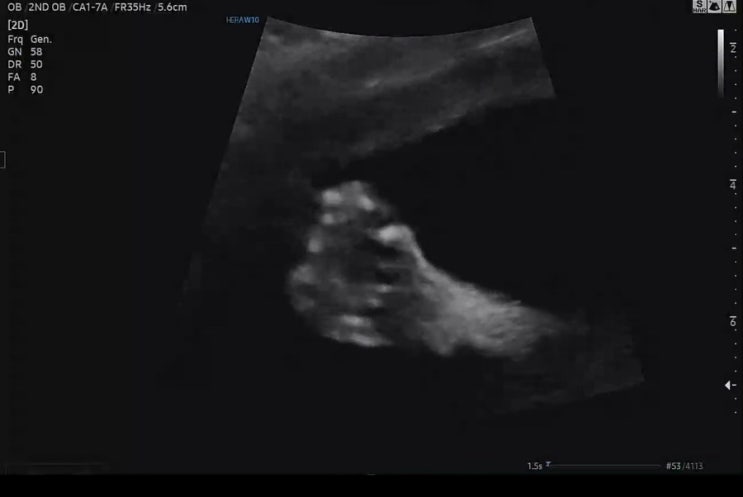

송파 고은빛/ 임신 22주 정밀 초음파 진행

임신 초기에는 사소한 걸로도 걱정이 되어 일주일마다 병원을 방문했는데 중기가 되니 태동도 느껴지고 해...